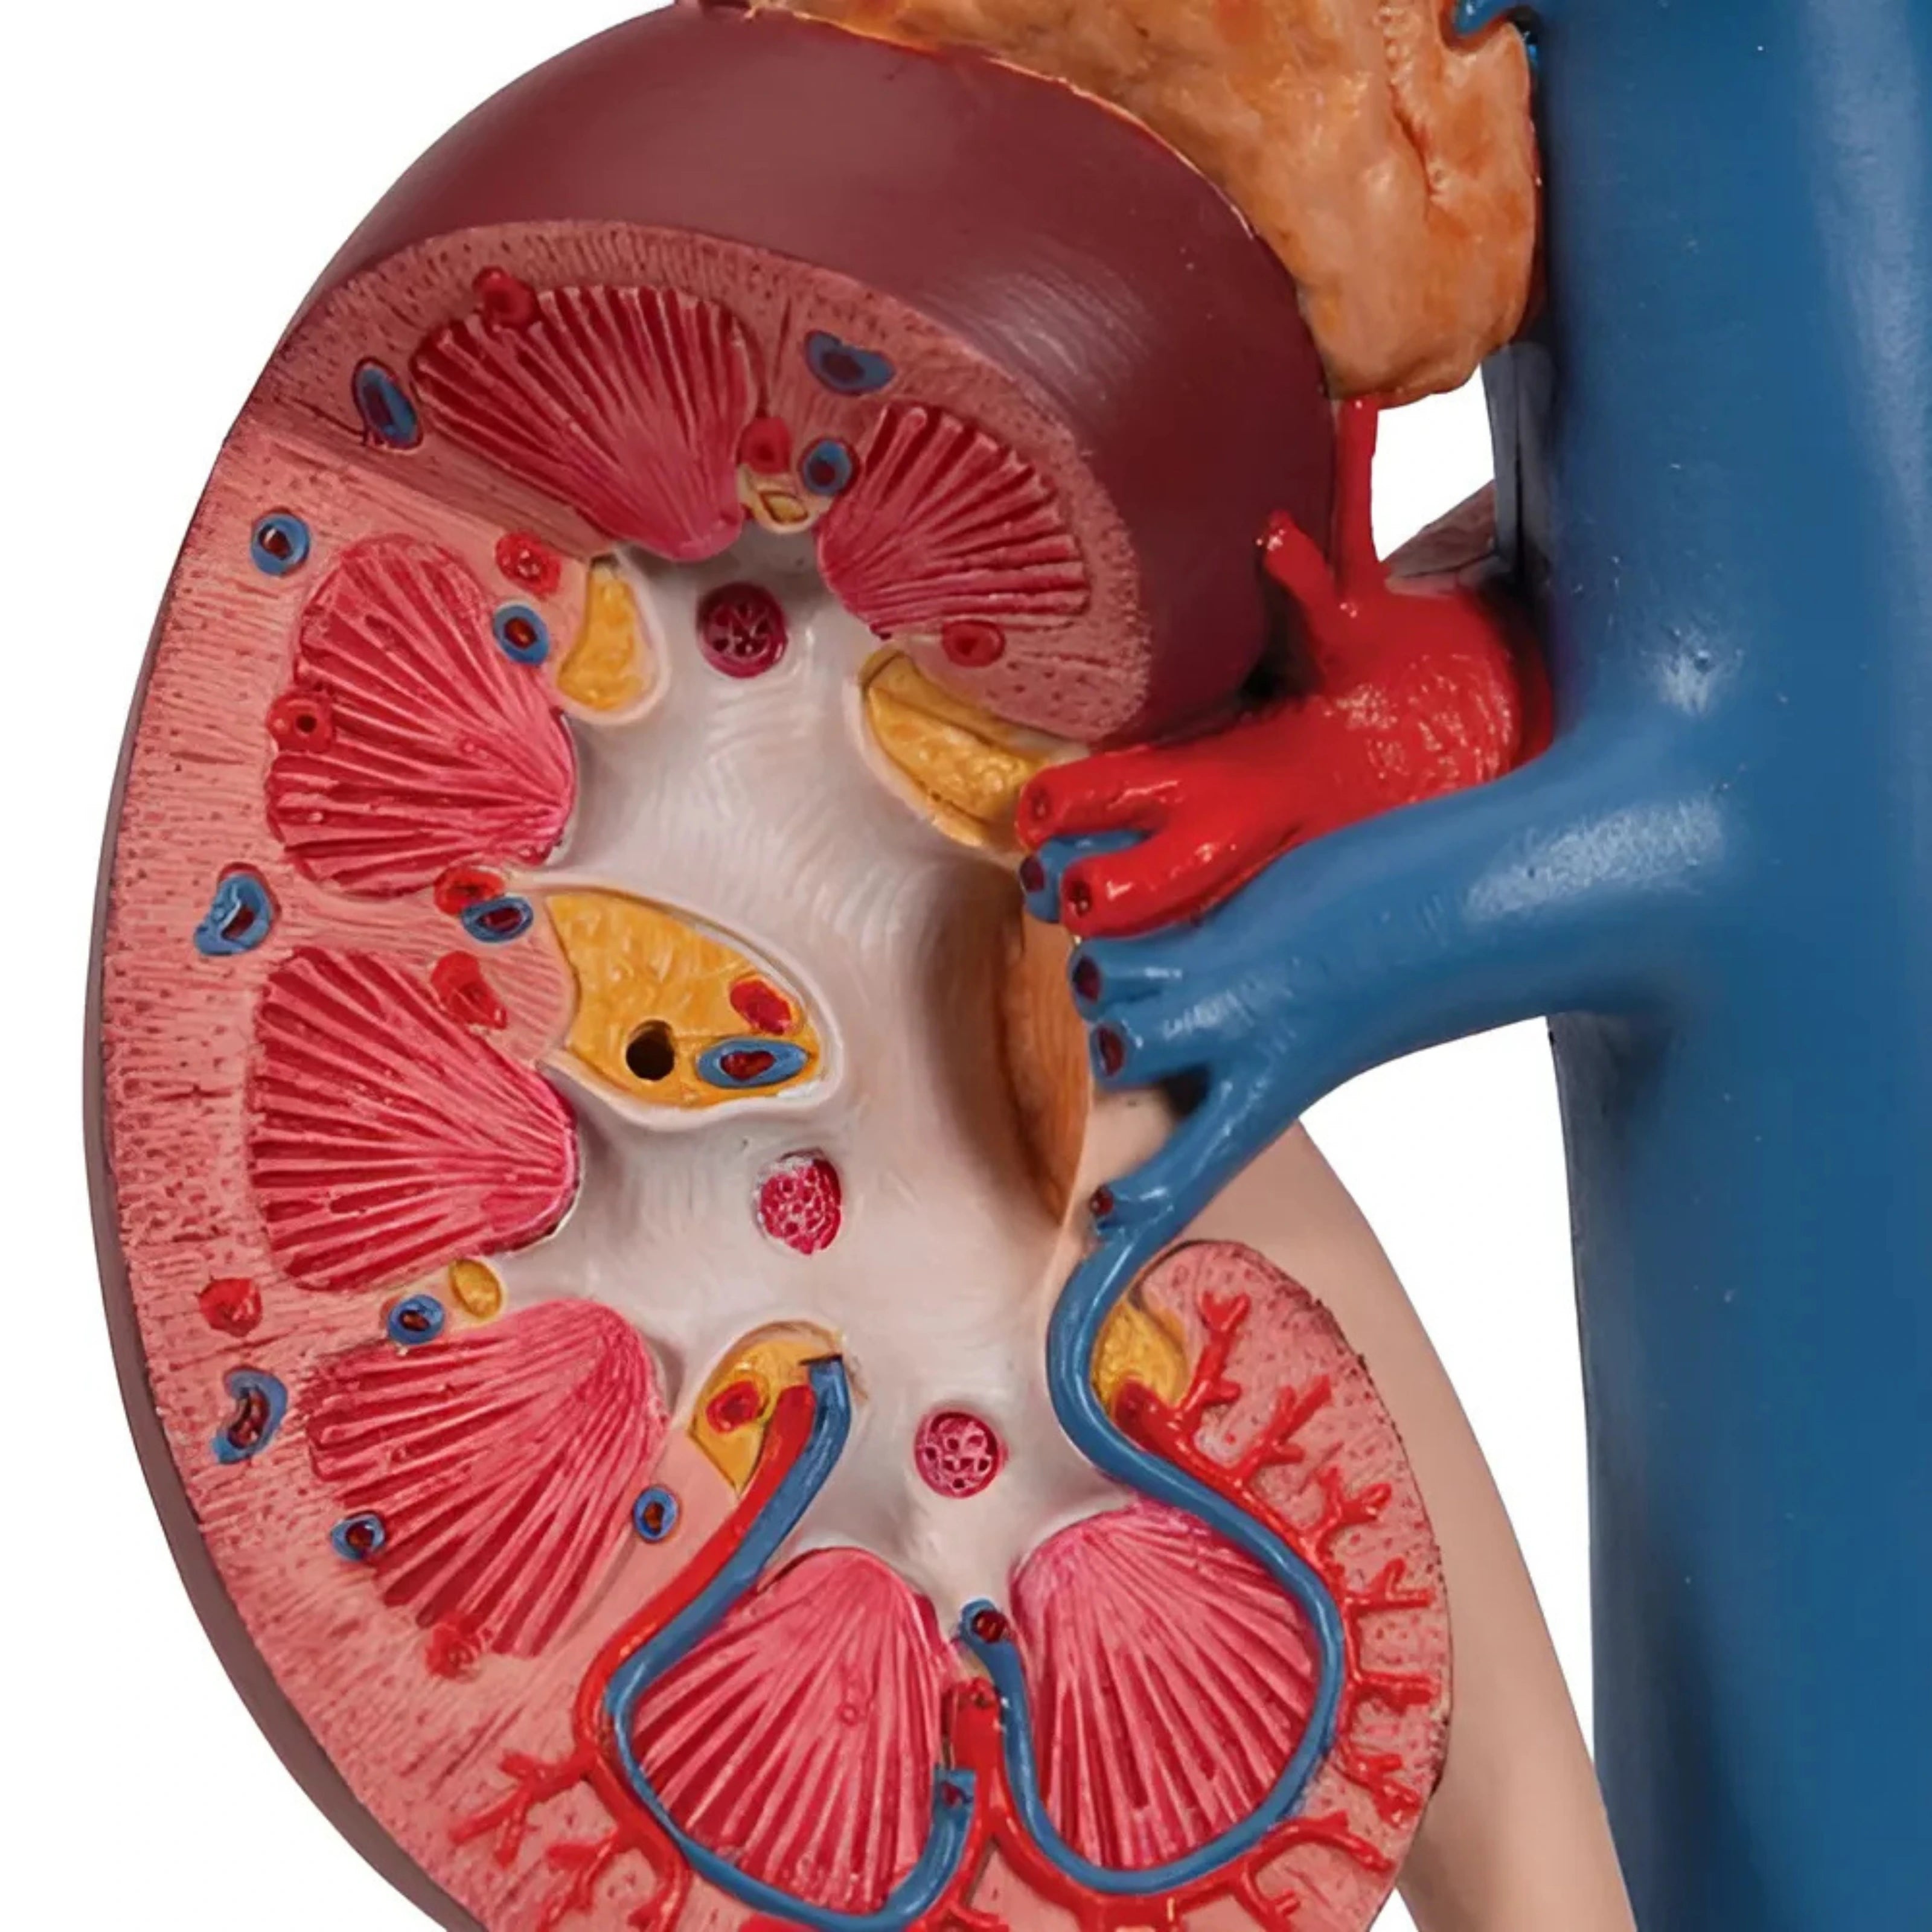

Riñones con Órganos Posteriores del Abdomen Superior (3 Piezas) - 3B Smart Anatomy

Precio de venta$12,993.33